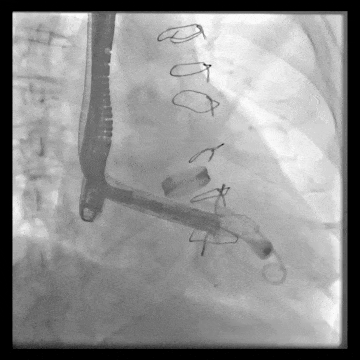

術中DSA顯示起搏器導線的干擾,右心室造影確定瓣環位置,操作空間小